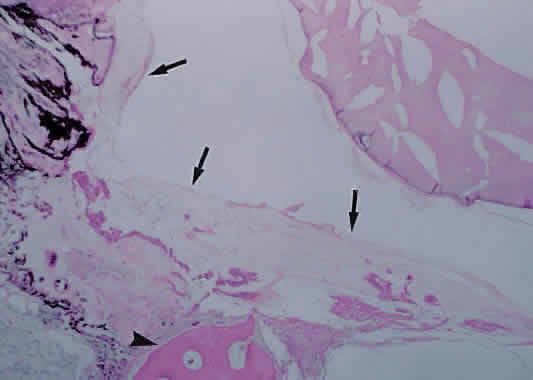

HISTOLOGY OF INFECTIOUS ENDOPHTHALMITIS

Histopathologic examination of eyes with acute bacterial endophthalmitis typically shows an infiltration of polymorphonuclear leukocytes with the formation of suppurative inflammation and destruction of ocular structures (Fig. 15). Depending on the duration of the inflammation, chronic inflammatory cells can be seen as well.

Fig. 15. A. Photomicrograph of an eye enucleated for acute purulent bacterial endophthalmitis. Cells at right of figure are polymorphonuclear leukocytes with admixed hemorrhage. There is destruction of the retina (arrow) (hematoxylin and eosin; × 31). B. Higher power showing purulent material composed of viable and degenerating polymorphonuclear leukocytes and exudative material (hematoxylin and eosin; × 500).